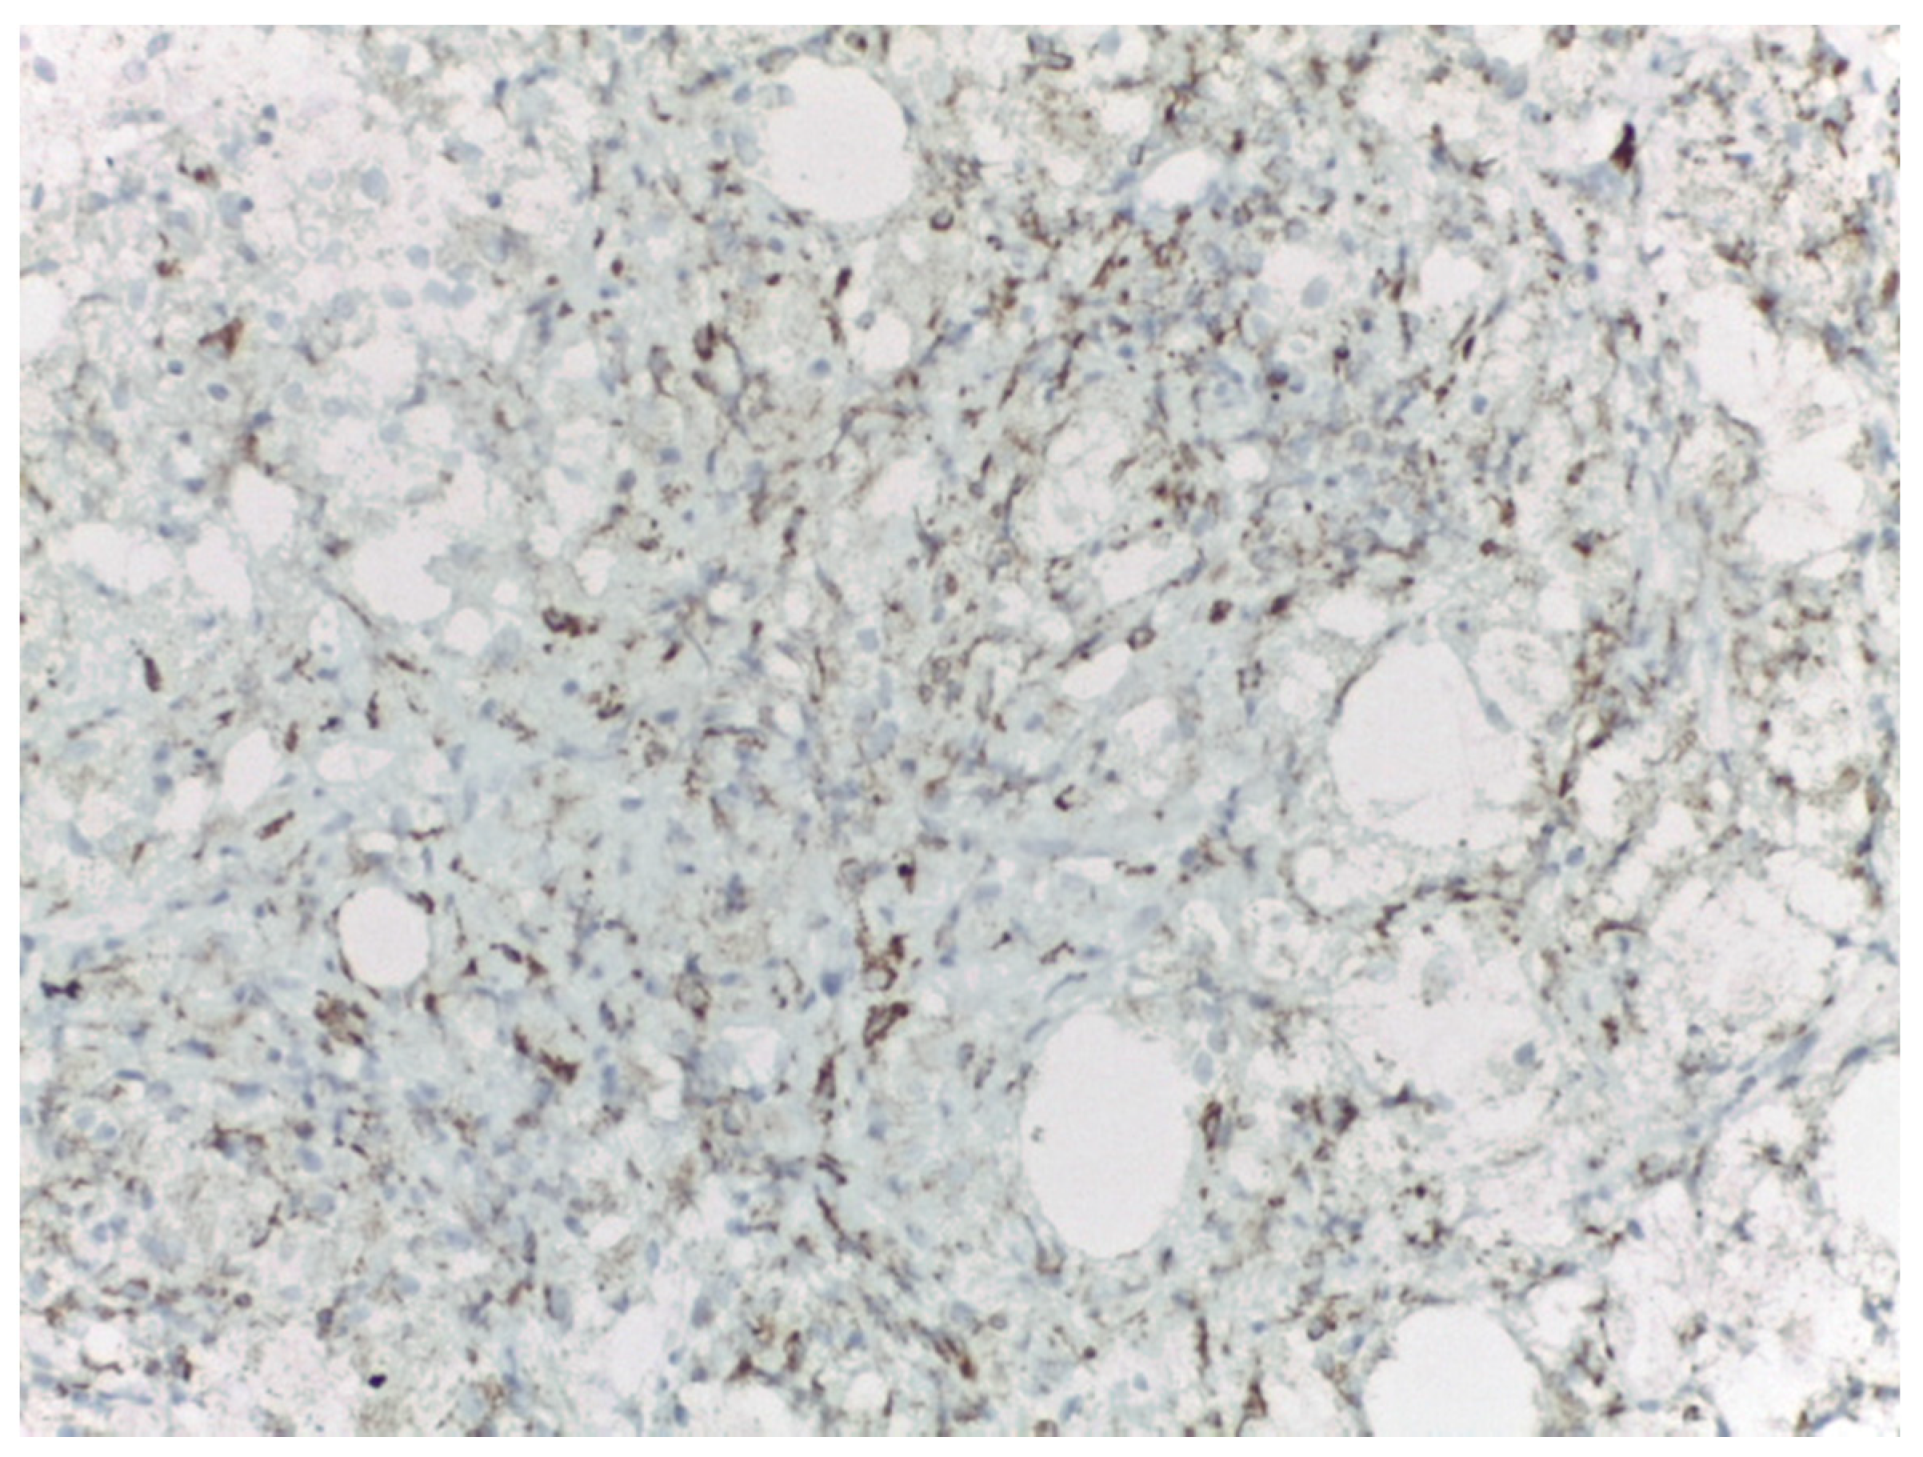

3. Case Presentation